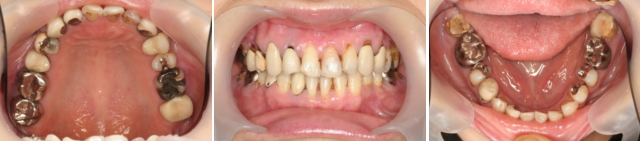

口腔内を診てみますと虫歯ではなく、噛み合わせの関係で奥歯に歯を揺さぶる悪い力がかかり、支えている骨にダメージを与えて歯周病を悪化させていました。まず先日書きました初期治療を行い、症状を安定させたのですが、歯にかかる悪い力はコントロール出来ませんでした。噛みあわせの治療のために、矯正治療が必要なことを話し理解していだだき、治療を開始しました。 仕事もされているため治療期間を短くしてほしいとの希望もありました。

専門的には、「反対咬合」と呼んでいます。また、上下の歯列はV字型になり、特に下顎の小臼歯は内側に倒れています。今までの矯正治療では歯を水平的に動かすことをしていますが、このようなケースは上下の噛み合わせの高さが低いために機能的に反対咬合となってしまっています。そのため、積極的に高さをあげる必要があります。その時に威力を発揮しますのがマルチループというテクニックです。通常2~3年かかる治療が1年2が月で終わりました。患者さんは 結果にとても喜んでいます。その後、問題がある奥の銀歯の歯の治療をすることとなりました。マルチループのテクニックは、ワイヤー(針金のようなもの)をベンドする(曲げる)のがたいへんですが、こんなに短期間で理想とするゴールにいける素晴らしいテクニックと感じています。

このように外見的な問題でない時でも、噛み合わせ治療のために矯正を行う場合があります。噛み合わせの安定は、治療結果の安定に大きく影響します。